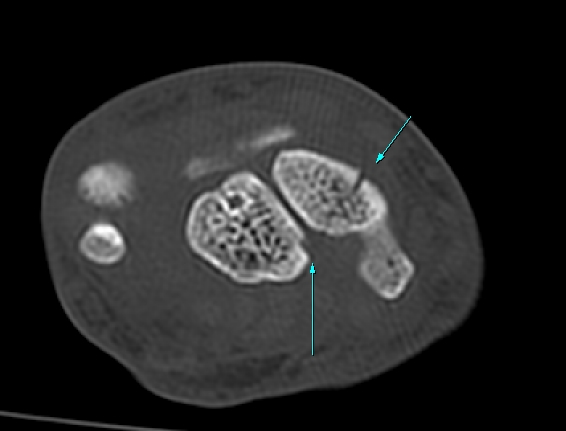

¼Õ¸ñ ¿ä°ñÃø ÁÖ»ó°ñ Á¾´Ü¸é °Ë»ç¿¡¼ ÁÖ»ó°ñ ÇÇÁú°ñ ¿¬¼Ó¼º ¼Ò½ÇÀÌ ¶Ñ·ÈÇÏ°í µ¿¹ÝµÈ ¿¬ºÎÁ¶Á÷ ºÎÁ¾ÀÌ °üÂûµÊ(»çÁø 3, 4)/